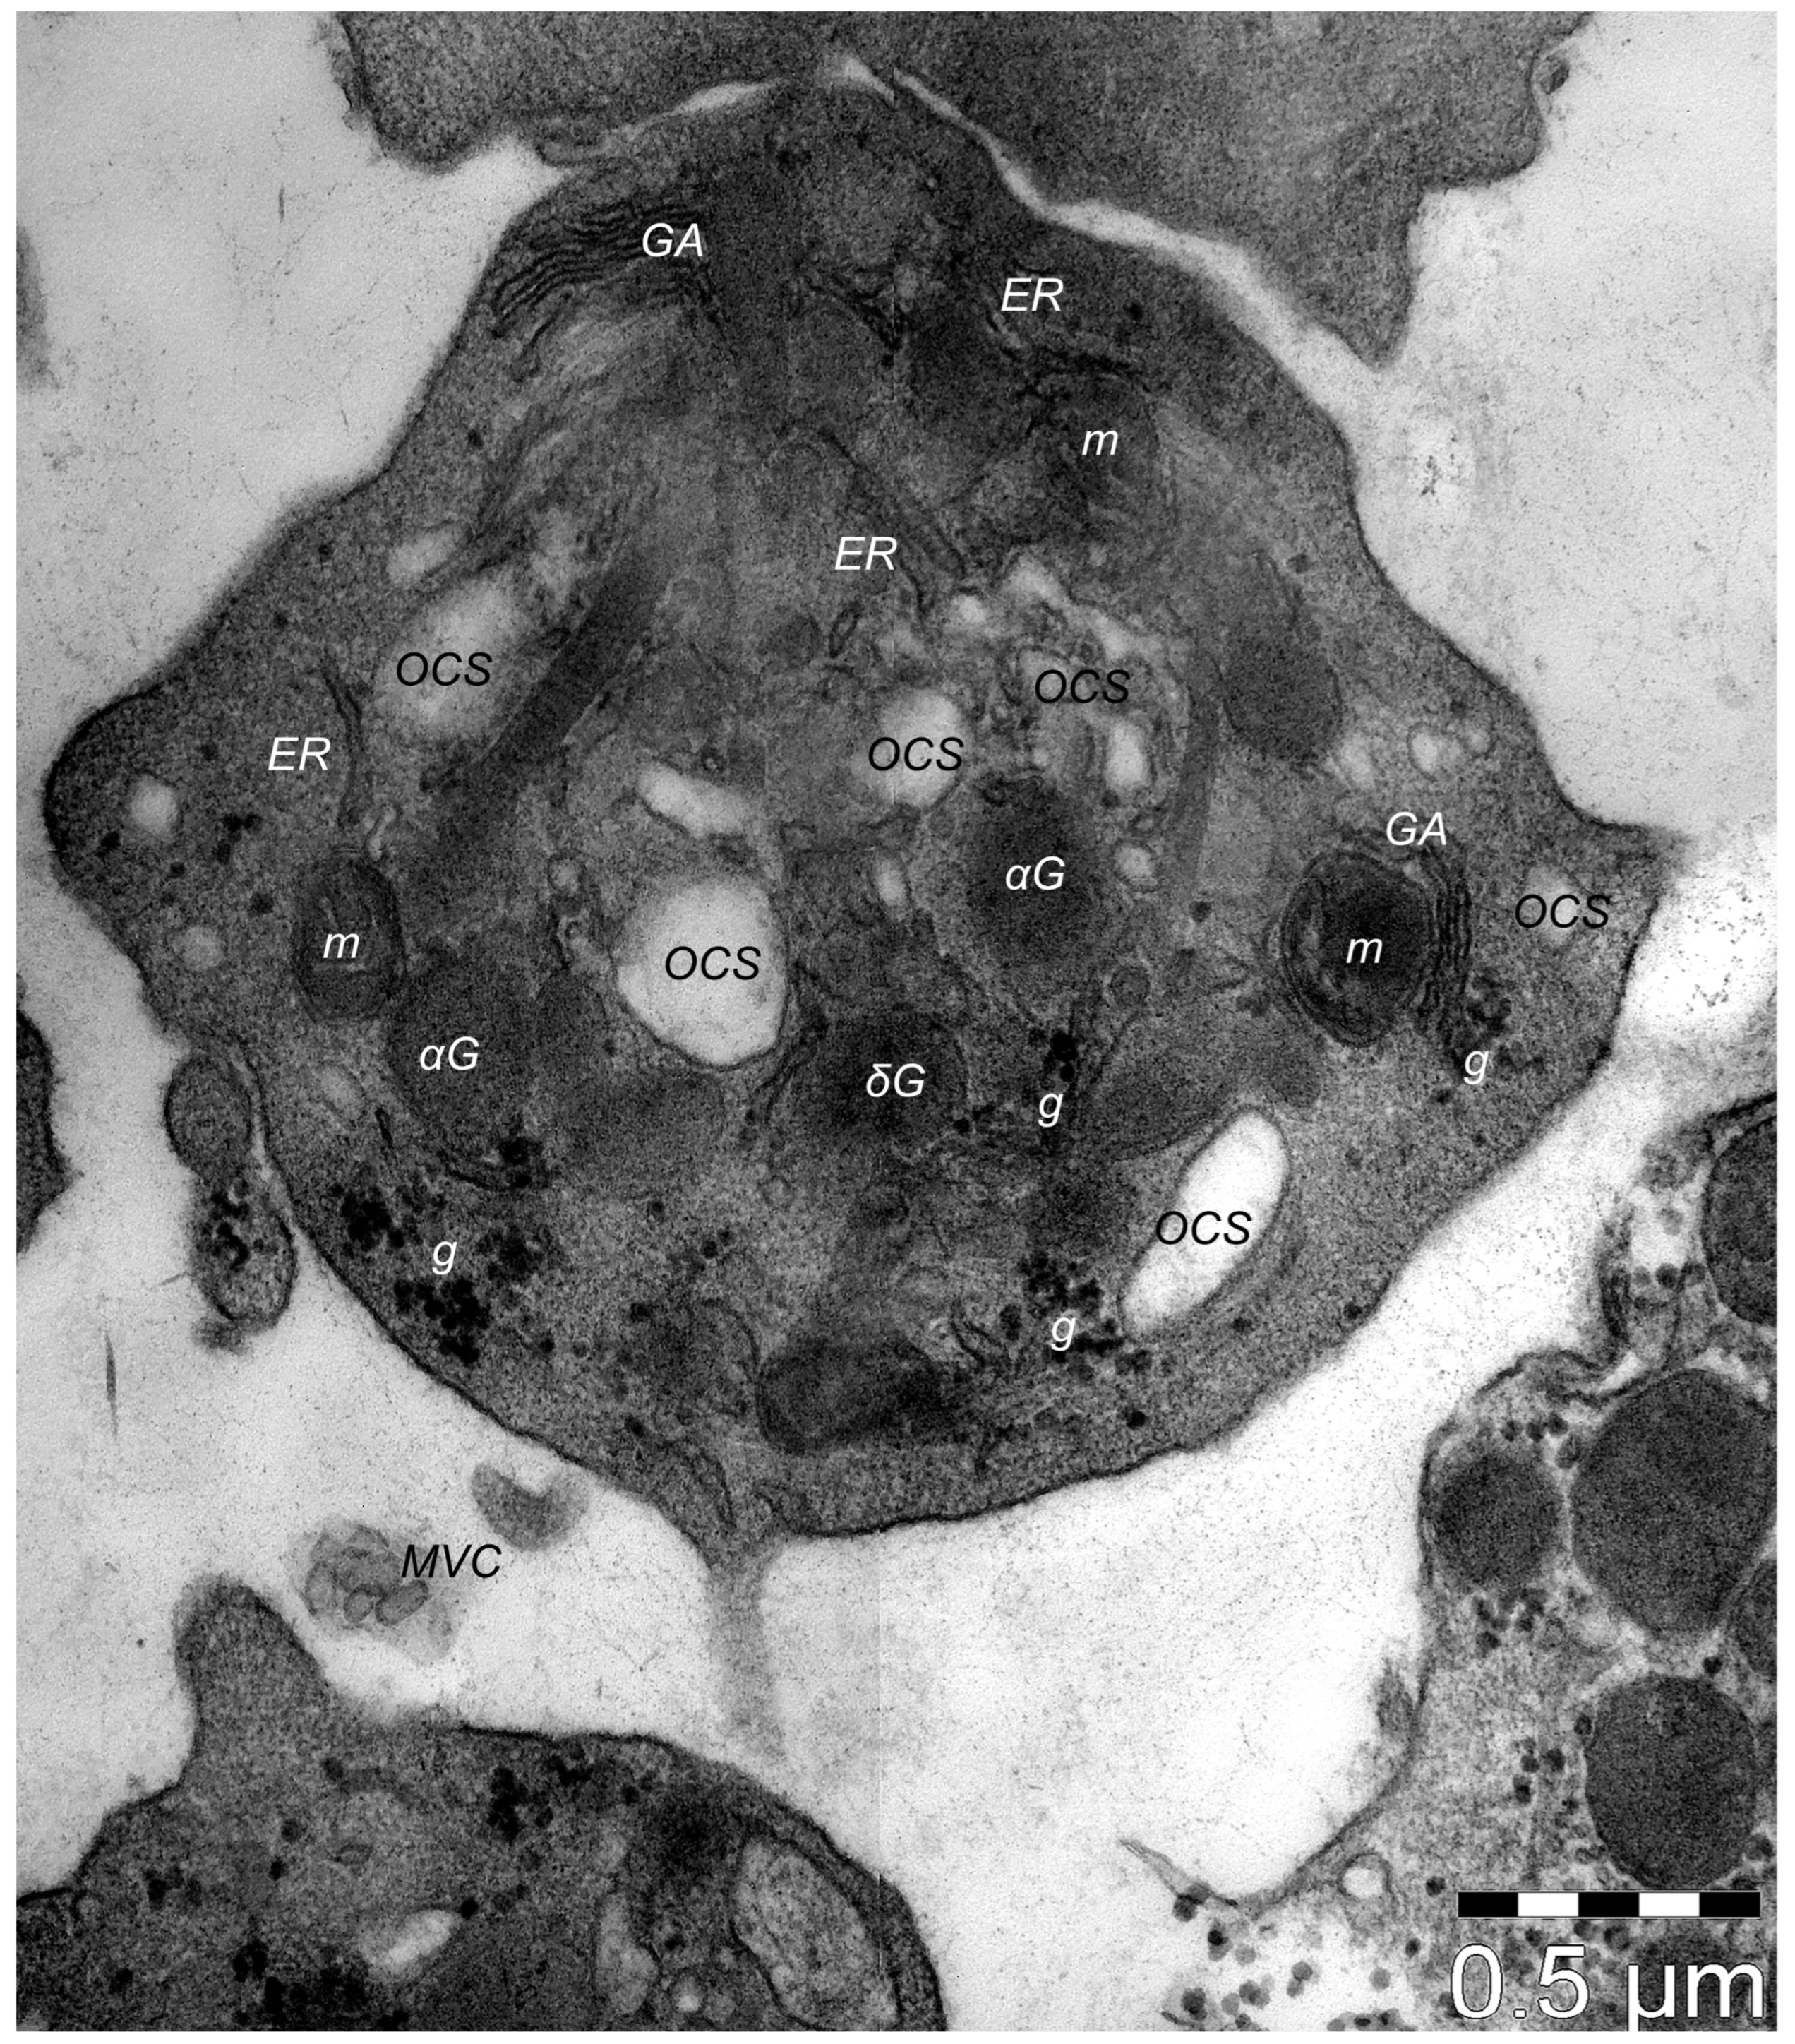

Platelets have fundamental roles in homeostasis and thrombosis. This is evident in tissue injury caused by trauma or ischemia, like in lesions produced by myocardial infarction or stroke, when the coagulation system and immune responses activate very early, initiating the healing process. Platelets (Figure 1) are fragments of thrombocytogenic megakaryocytes that are among the first cells that penetrate and accumulate within the lesioned tissue and, when activated, release a multitude of biologically active mediators into their microenvironment [1]. Apart from these traditional roles, in recent years, new and important ones have surfaced. Thrombocytes, through their growth factors (GFs), cytokines, antibiotic peptides, and extracellular matrix modulators are involved in a cascade of events starting with angiogenesis in damaged tissue, stabilizing blood vessels and restoration of connective tissue, the transformation of mesenchymal stem cells into fibroblasts, etc.

The Golgi apparatus (specifically, the trans-Golgi network) represents the origin of α-granules. Thus, they have a secretory phenotype similar to late endosomes and lysosomes and are considered lysosome-related organelles similar to basophil granules, azurophil granules, melanosomes, Weibel–Palade granules, Odland bodies in keratinocytes, and lamellar bodies in type I pneumocytes [19]. Usually, they demonstrate similarities with these organelles, like endosomal filiation, the acid content due to the presence of various enzymes, and the protein composition of the lysosome membranes [20]. They develop from the former small granular precursors found within the cytoplasm of thrombocytogenic megakaryoblasts (MKs), which maturate α-granules and deliver them, by thrombopoiesis, to platelets for final packaging. The organelles that originate α-granules either accumulate different compounds via synthetic routes (e.g., von Willebrand Factor, β-thromboglobulin, or platelet factor 4—PF4), or acquire them by endocytosis, (e.g., albumin, fibrinogen, or immunoglobulin G) [21]. In terms of morphology, ultrastructural studies have indicated a few different types of α-granules, including tubular, spherical, and multivesicular subtypes [22]. The matured granules are released from the platelets in different pathological processes of hemostasis and wound repair, inflammation, tumor metastasis, or angiogenesis [23]. The dynamics of platelet secretion indicates their roles and functions, and their performant action in all processes they are involved in. Thus, we presume that the number, sequence, and amount of each of these factors that are released from platelets are orchestrating the steps of tissue regeneration/repair in terms cellular and molecular phenomena that feature in the healing process.

Dense granules are electron-dense spherical vesicles of about 200 nm and are the second most abundant platelet organelle. δ-granules contain molecules involved in both homeostasis (evidenced by the bleeding propensity, which features in a few hematologic diseases—e.g., Chediak–Higashi syndrome, which exhibits a deficit of platelets’ dense granules) and thrombosis through the inhibition of arterial thrombosis by ADP, etc. Platelets’ δ-granules are maturated within MKs and then transferred to enucleated cells. The early endosomes contribute to the formation of δ-granules [147] and they also share lysosomal features; thus, dense granules are considered lysosome-related organelles, having and acidic content and housing lysosomal enzymes (e.g., tetraspanin CD63) [148].